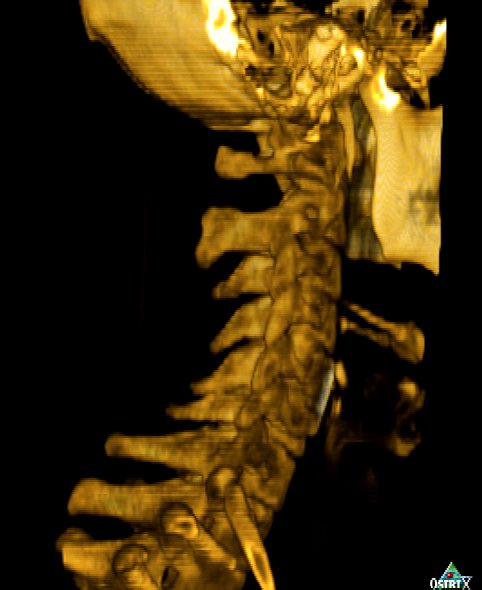

When I look left, my left arm goes numb. So they sent me in for more scans. I learned first-hand that MRIs induce electrical currents in titanium, which can be quite interesting when it's pointing at your spinal cord. Some minor findings, but nothing major warranting more surgery. Which is good. As long as I don't need to look left.

Here's a movie (30MB) we made from the CT data with which to entertain you. Please enjoy it with much glee so when I die of thyroid or brain cancer I'll know deep down it was all worthwhile. Click on the image to view or download. (It's just a 360 rotation, alas. Sorry, no singing skulls.)